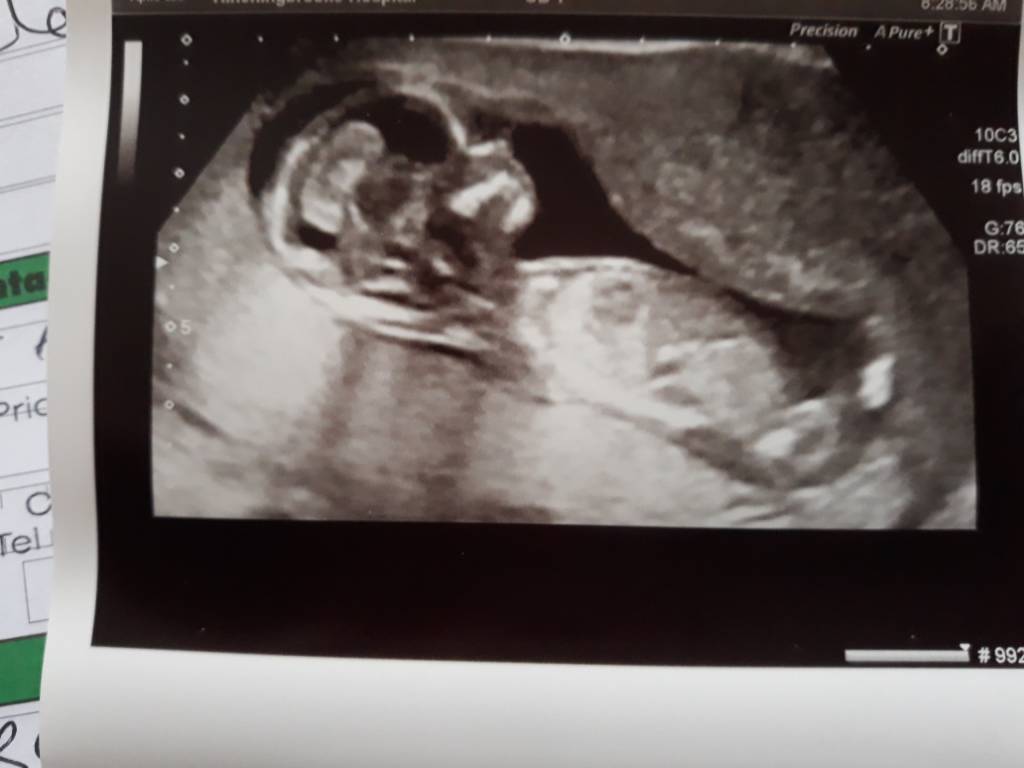

Tak wiec wizyta z 29.09 - gdy mój bobasek miał 13 t 2d.

Ktos dopatrzył sie ze ssie kciuk![]()